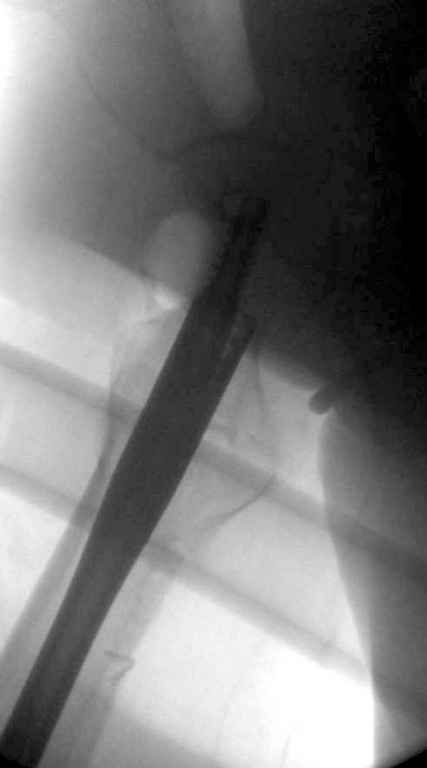

Хотелось бы увидеть снимки непосредственно после операции.

Перелом тут больше подвертельный. Нагрузка без торцевого упора на уровне перелома привела к телескопированию отломков на стержне. Ну и варус небольшой тоже свою лепту внес - если бы его не было, контактирующие латеральные стенки обоих отломков предотвратили бы укорочение, да и срослось бы за пару месяцев. А раз не срослось, упора отломков нет, более слабым местом оказались не нижние винты, а кость в головке и шейке. Так что надо было хотя бы удалить нижние винты до начала полной нагрузки.

На мой взгляд, причиной телескопирования явилось несоответствие диаметра гамма нэйл с диаметром канала подвертельного отдела бедра: обратите внимание на величину протрузии шеечного винта и величину медиализации дистального фрагмента - они одинаковы, смещение или телескопирование фрагментов происходило до того момента, пока гамма нэйл не упёрся в медиальный кортекс и образовалось пространство между латеральным

кортексом и латеральной поверхностью гвоздя.

Диаметр гаммы в диафизарной части ~11 мм. А диаметр канала, тем более у пожилых с остеопорозом, может быть мм 15. Даже рассверливать обычно не приходится, после формирования широкого канала в вертельной области можно сразу толкать гвоздь, он влетает, как карандаш в стакан. Так что соответствия диаметров не бывает никогда. Однако представленная ситуация случается далеко не каждый раз. Если гвоздь в центральном отломке входит чуть медиальнее верхушки вертела, и идет вдоль передне-латеральной стенки центрального отломка, то все будет хорошо.

В приложении похожий пример, к счастью, пациентка появилась не после, а "за полчаса" до протрузии. Пересинтезировали с исправлением ошибок.